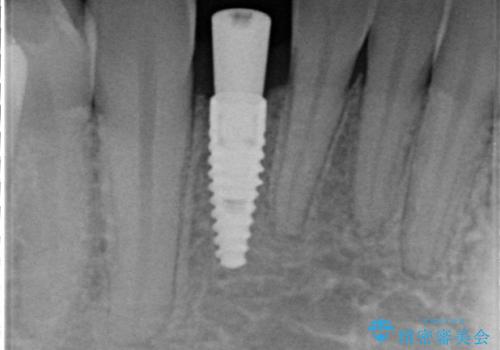

- 45万円(税別) 内訳:ストローマンインプラント(1本)20万円、ジルコニアクラウン10万円、シリンダーTeC 2万円 ジルコニアカスタムアバットメント10万円 ホワイトニング(エクセレント)3万円費用は治療当時の料金となります

ブリッジにすることも可能でしたが、両側の歯が天然歯であること、また、事前に矯正で噛み合わせを整え、幅も確保していたこと、CTにより骨の厚みがある程度あったことを踏まえ、インプラントも可能であるとお話しし、選んでいただきました。

唇側の骨増成もしっかり行い、前歯部インプラントによくある、歯茎が下がって見えることもない、審美的なインプラント補綴ができました。